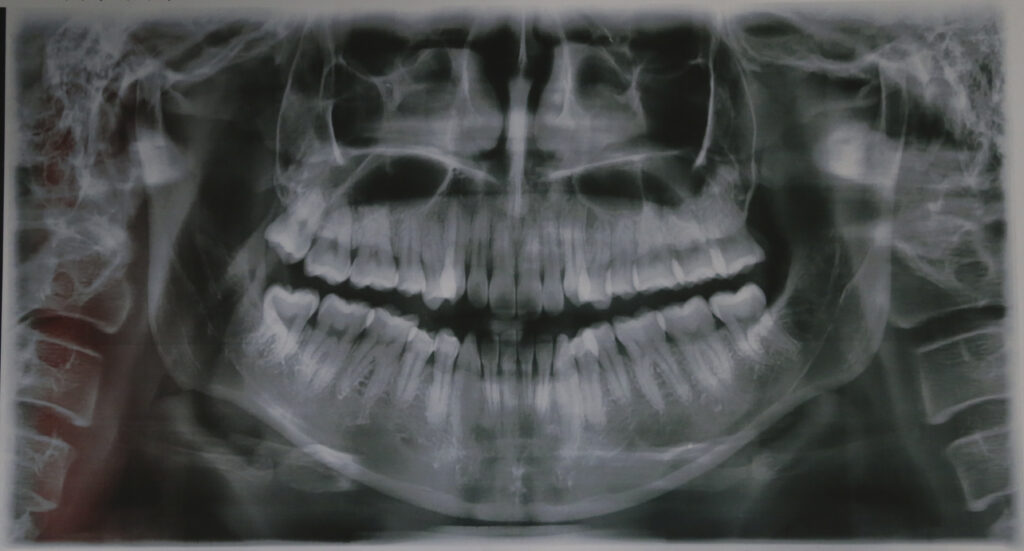

Phân tích phim cho thấy sai hình xương loại III